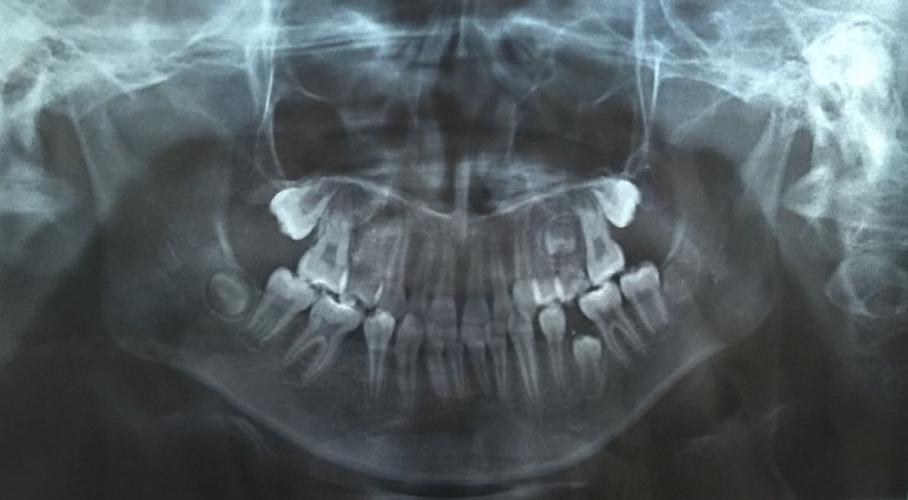

圖片由院方提供

兒童口腔科副主任醫(yī)師王銳副教授為琦琦拍攝了一張曲面斷層片,發(fā)現(xiàn)琦琦左下后牙區(qū)有一顆牙齒因間隙不足阻生,建議家長(zhǎng)接受矯正調(diào)節(jié),擴(kuò)開(kāi)間隙,觀察阻生于頜骨內(nèi)的牙齒是否可以順利萌出。調(diào)節(jié)過(guò)程相對(duì)復(fù)雜,調(diào)節(jié)周期較長(zhǎng),需要每隔一個(gè)月復(fù)診一次。“孩子今年上初中,課業(yè)壓力越來(lái)越大,但既然牙齒出現(xiàn)這么嚴(yán)重的問(wèn)題,擠時(shí)間也要積極配合醫(yī)生調(diào)節(jié)?!泵鎸?duì)這種情況,琦琦媽媽無(wú)奈的說(shuō)。

據(jù)王銳副教授介紹,孩子的乳牙脫落要及時(shí)到醫(yī)院拍攝曲面斷層片觀察是否存在乳牙早失、恒牙阻生或發(fā)育異常等情況,一旦發(fā)現(xiàn)乳牙早失必須及時(shí)制作間隙保持器保留牙齒間隙,給恒牙足夠的萌出空間,避免嚴(yán)重后果。